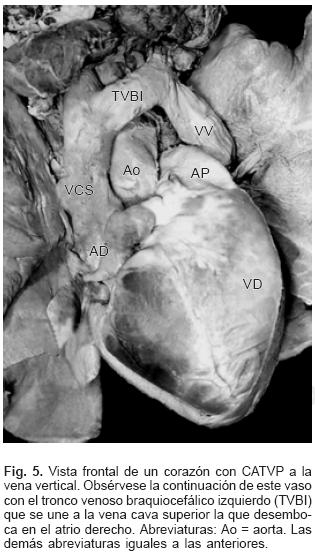

En todos los especímenes el SVP estuvo independiente, separado del atrio izquierdo y ubicado por detrás y un poco por encima de esta cámara cardíaca incompleta y pequeña (Figs. 1 y 2). El SVP se continuó con un vaso colector que siguió diferentes trayectos según el sitio de conexión anómala; en el tipo a vena cava superior el colector ascendió por detrás del bronquio derecho o del izquierdo según la posición de esa vena; en dos especímenes la obstrucción del colector fue intrínseca por estrechez del mismo en el sitio de su desembocadura (Figs. 3A y 4) y en un espécimen el colector siguió un trayecto anómalo entre la rama derecha de la arteria pulmonar y el bronquio derecho lo que provocó obstrucción extrínseca en el mismo (Fig. 3B). En el sitio de conexión anómala a la vena vertical el SVP recibió las venas de ambos pulmones y a través de un colector corto se continuó con la vena vertical ubicada del lado izquierdo, ésta a su vez lo hizo con el tronco venoso braquiocefálico izquierdo que desembocó en la vena cava superior y ésta en el atrio derecho (Fig. 5); en un espécimen existió obstrucción intrínseca en la vena vertical (Fig. 6).

La desembocadura anómala a vena cava superior se puede realizar en varios niveles: por encima del cayado de la vena ácigos, por debajo de la misma y justo en su entrada al atrio derecho. En la CATVP al seno venoso coronario, éste se verticaliza en su extremo distal y su dilatación es debida al flujo venoso pulmonar; la estenosis intrínseca del colector unido al seno coronario ocurre con poca frecuencia.6,7,10,25 En la CATVP a vena vertical la continuidad de ésta con el tronco venoso braquiocefálico izquierdo y con la vena cava superior derecha conforman la imagen cardioangiográfica de la cabeza del "8" o del "muñeco de nieve", mientras que su cuerpo lo forma la silueta cardíaca.8,10,19,35